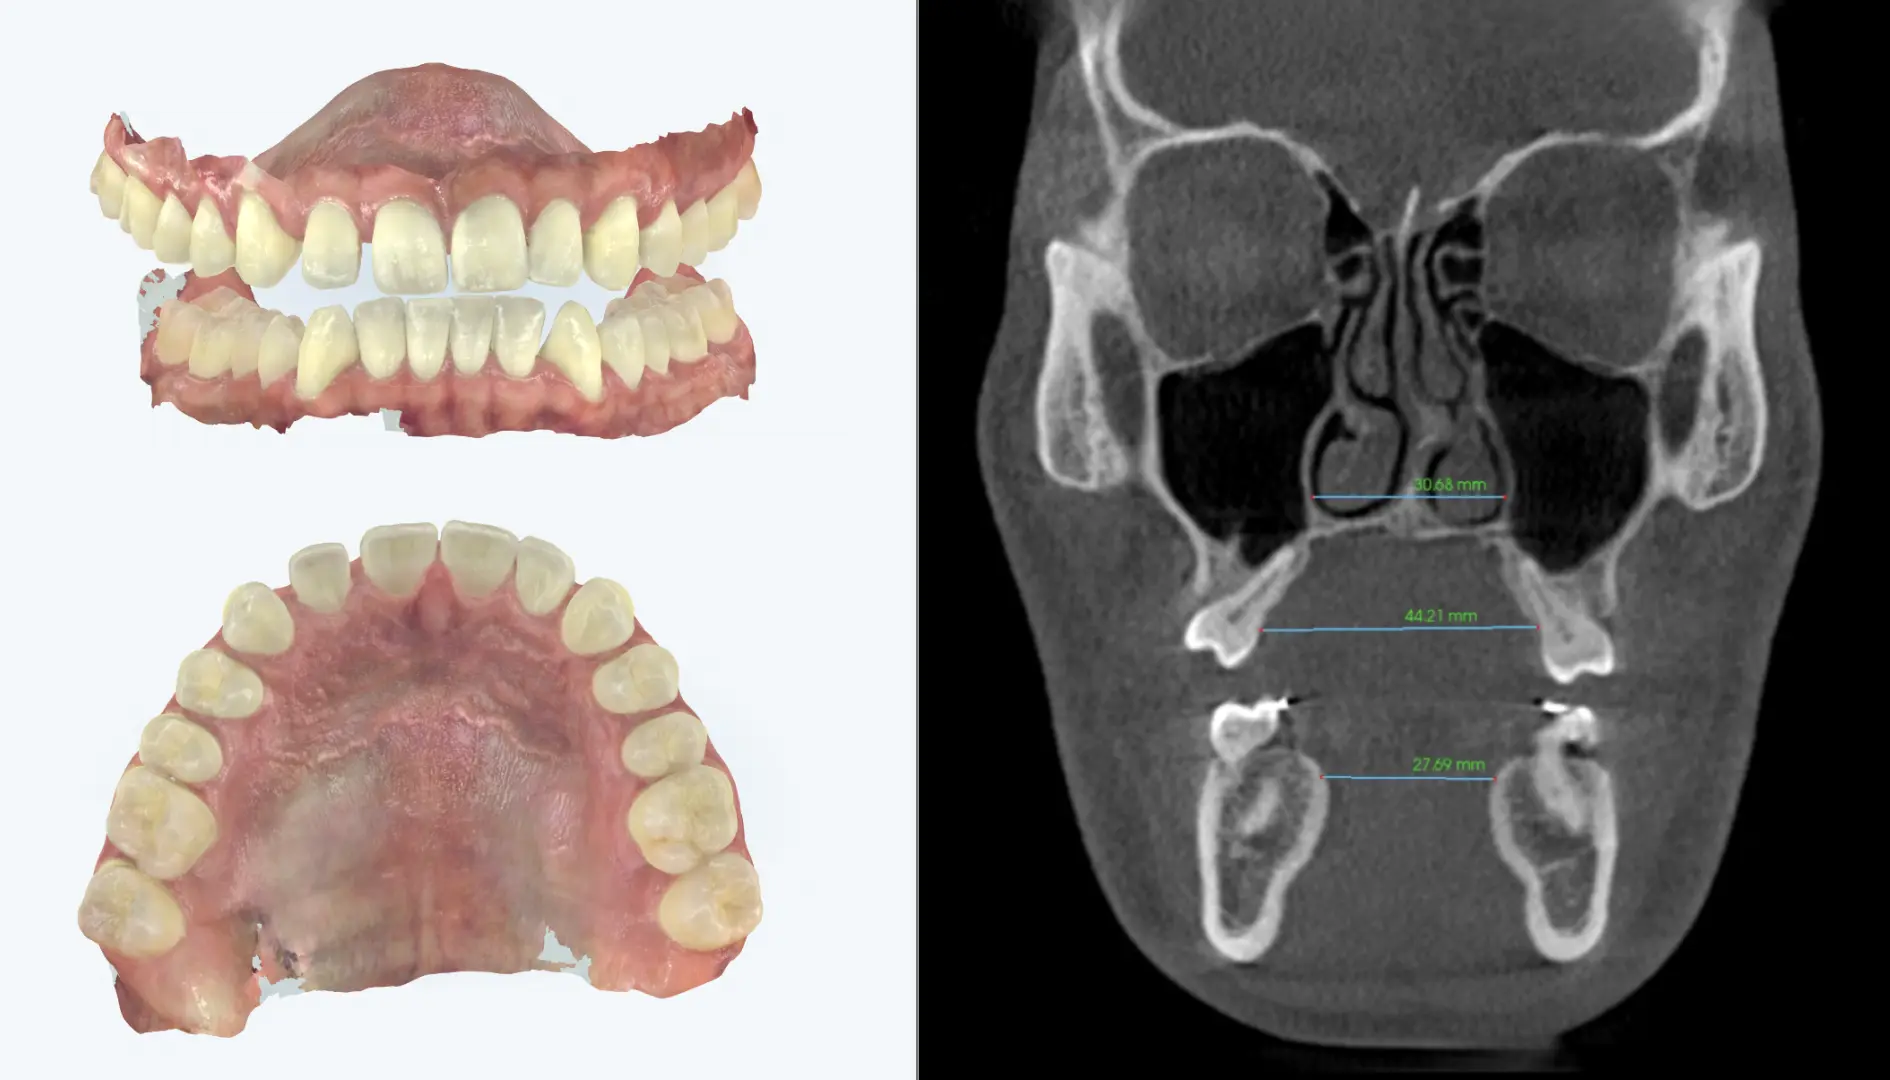

Dental models and coronal X-ray showing tooth-borne expansion with outward tipping instead of true skeletal widening

As shown in the image on the left, a tooth-borne expander can create a wider palate and more tongue space, but the X-ray demonstrates that much of this change is achieved by pushing the teeth outward rather than producing true skeletal expansion.

Our office commonly coordinates skeletal expansion together with aligner based tooth movement rather than waiting until expansion is fully complete before addressing dental alignment. This approach allows arch development and tooth coordination to occur simultaneously, so the teeth can be guided into position as the maxillary width is changing.

By sequencing treatment this way, the space that opens between the front teeth is often managed more actively than it is in a traditional expansion-first workflow. The goal is to support skeletal correction while keeping the dental response more controlled, improving arch coordination as expansion progresses, and reducing the need for a separate large-gap phase before alignment begins.

• Expansion and tooth movement are planned together rather than treated as completely separate phases, and rubber bands can be used when needed to help coordinate the bite.

• Aligner staging helps guide incisor position and arch coordination during active width development.